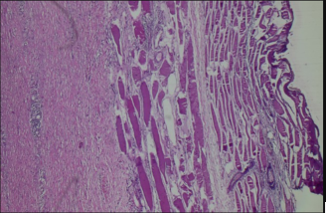

A 53-year-old male presented with complaints of abdominal pain for 2 months and was found to have a left adrenal complex cyst on ultrasonography of the abdomen. He was admitted to the hospital for adrenal hormone examination, which showed normal adrenal function tests. Contrast computed tomography (CT) of the adrenal gland showed a peripherally enhancing multiloculated cystic lesion in the left adrenal gland. An adrenal endothelial cyst was kept in the differential diagnosis. The mass was surgically excised via laparoscope with complete excision of the right-sided retroperitoneal adrenal mass. Grossly, the adrenal mass was lobulated with a cut surface showing predominantly adipose tissue, interspersed grey-white firm areas, and a cystic area with a calcified wall. Histologically, the representative sections revealed derivatives of all three germ layers, including mature epidermal structures, glandular epithelium, bone, cartilage, skeletal muscle fibers, adipose tissue, seromucinous glands, as well as multinucleate giant cells, pigment-laden macrophages, and areas of necrosis. No areas of immature neuroepithelium or somatic malignancy were seen. (Figure. 1, A-D). This case report has been reported in line with the SCARE criteria [4].

Figure 1: Microscopic examination, H&E stain, 10X: Reveals derivatives of all three germ cell layers, including mature epidermal structures, glandular epithelium (A), bone, cartilage (B), adipose tissue, and seromucinous glands (C), skeletal muscle fibers (D).